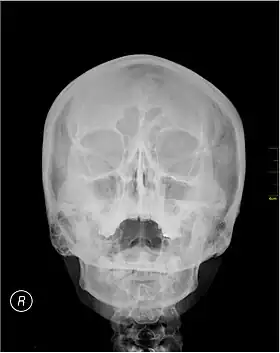

Waters' view

A Waters' view radiograph showing the paranasal sinuses

Waters' view (also known as the occipitomental view) is a radiographic view of the skull. It is commonly used to get a better view of the maxillary sinuses. An x-ray beam is angled at 45° to the orbitomeatal line. The rays pass from behind the head and are perpendicular to the radiographic plate. Another variation of the waters places the orbitomeatal line at a 37° angle to the image receptor. It is named after the American radiologist Charles Alexander Waters.